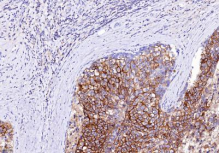

抗原-抗体免疫染色 | 免疫组化 |

|